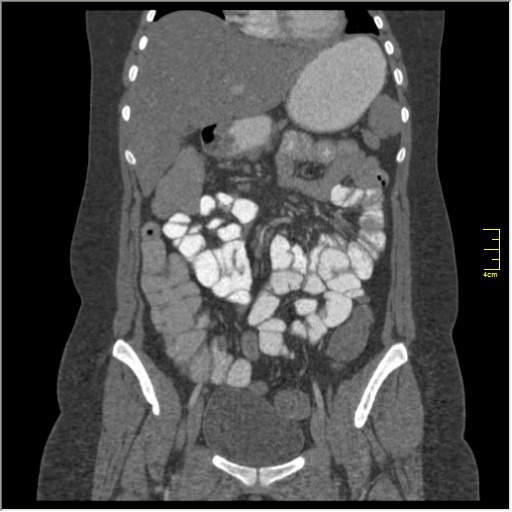

КТ энтерография

Демонстрационные изображение, оцените возможности метода! Толщина среза реконструкции 0.5-1 мм.